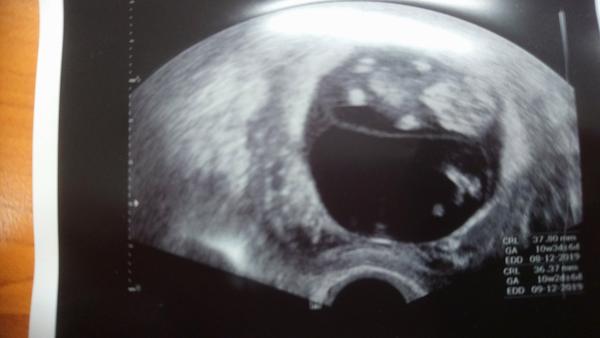

Tak jsem se vratila z kontroly, vsechno v poradku, mimi ma 2,5 cm, myslim ze 9+0 tt. Bylo krasne videt, vrtelo se... Laska na prvni pohled 🙂 A dokonce mi je od vikendu o trosku lip, po naprosto hroznych 14-dnech... Takze ja mam dnes radostny den, a preju taky radostny vam vsem 🙂

Ahoj holky! Tak druhá kontrola je úspěšně za námi má dvě ruce dvě nohy tak snad to bude dobrý 😀 Bylo super se dívat na té obrazovce jak se tam furt vrtí, málem jsem se tam rozbrečela 😅 Momentálně jsem 10+4 a genetika mě čeká za tři týdny, všem ostatním co je čeká kontrola přeji ať je vše O.K